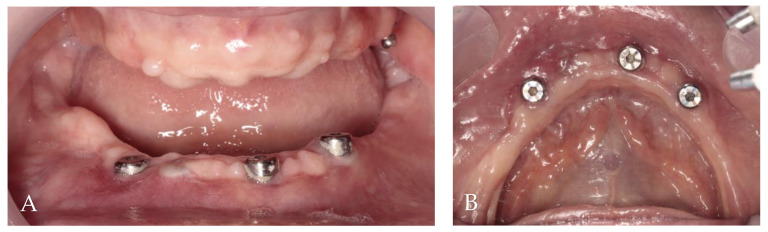

Two months post-op intraoral photographs: (A) frontal view; (B) occlusal view.